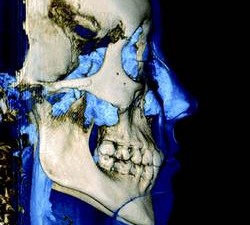

3-D software can shade images to differentiate varying densities of facial structures. Grayscale shading provides the ability to view the relationships of common internal anatomy. Traditional CT imaging renders an 8-bit grayscale (256 shades) or 12-bit grayscale (4,096 shades). Present-day scanners render images in 14-bit grayscale, providing 16,384 shades. Color coding the image by density further distinguishes anatomical structures, enabling the clinician to view pertinent anatomy while planning implant cases, such as nerves and nasal cavities, and mandibular and maxillary dimensions. Segmentation literally cuts the volume rendering, conceding top views, side views, and CT slices that produce unlimited axial, coronal and sagittal views. CBCT slices are as thin as 0.1 mm, compared to 1 mm for a conventional fan CT scan.

CBCT imaging provides comprehensive data and the ability to dynamically manipulate that data, viewing anatomy from multiple perspectives. Diagnosis of TMJ condition and disorder or jaw pathology along with the evaluation of orthodontic cases, airways, impacted teeth and periodontal defects are all facilitated through the use of CBCT imaging.

CBCT imaging is the ideal radiological modality for implantology due to the high quality of the produced images, software capabilities, and lower doses of radiation exposure. Two of the hottest topics regarding CBCT and implantology are virtual surgery planning and surgical guides. A virtual surgery can be performed with special software applications that enable dentists to evaluate the quality of bone through density shading and dimensions of bone can be recorded accurately with 1:1 measurement tools. It identifies common internal anatomy needed to evaluate implant placement including the jaw boundaries, adjacent teeth, nasal fossa, mandibular canal, maxillary sinus, mental foramen, and incisive canal. It also detects pathology to be avoided for implant health. Therefore, before the surgery, the clinician can confirm the appropriate implant size, location and angulation, and that plan can be fed to a 3-D printer to produce a surgical guide or stent for use during the actual surgery.